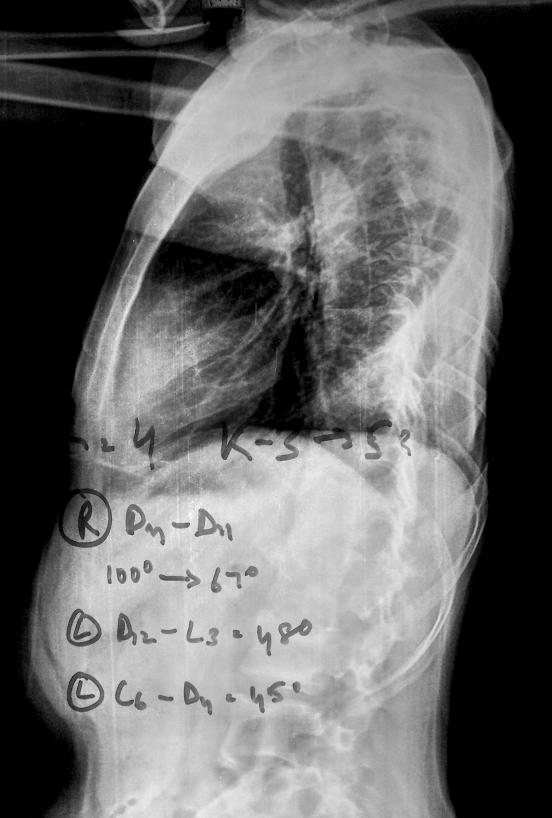

Standing erect Dorso-lumbo-sacral spine PA & Lateral views with planning. CT also done.

Pre-op Lat

Planning